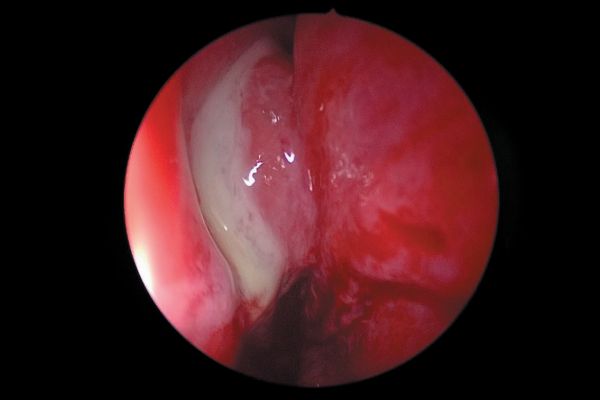

Imagen clínica de la preparación y sellado del istmo en la raíz mesial de molares mandibulares durante la cirugía endodóntica